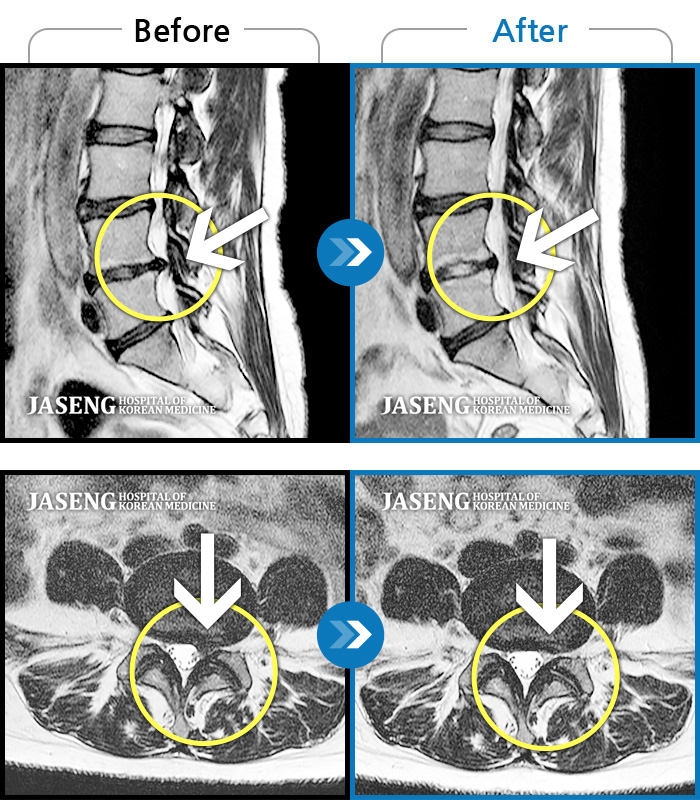

Before

After

환자에게 사전 동의를 받아 동일 조건에서 촬영되었습니다.

개인에 따라 치료 후 부작용이 발생할 수 있으니 의료진과 상담 후 치료를 진행하시기 바랍니다.

앉아있을 때 좌측 허벅지가 너무 아프고 야간통도 있다. 허벅지 뒤쪽 감각이 무디고 다리 힘도 빠진다.